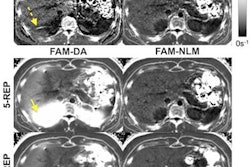

The graphic shows the segmentations of an MRI scan (A) with the manual (B) and the automatic variant (C). Panel D illustrates the comparison between manual and fully automatic segmentation. The green pixels indicate the areas of concordance, while the red pixels represent the areas of deviation. Image courtesy of Dr. Niklas Verloh.Many of these 3D analyses require segmentation of the organs. Organs are subdivided into individual anatomical or functional sections to provide the requesting physician with the desired information. This segmentation takes a lot of time if the radiologist has to manually do it. However, CT software programs are now available, which can at least partially automate segmentation.